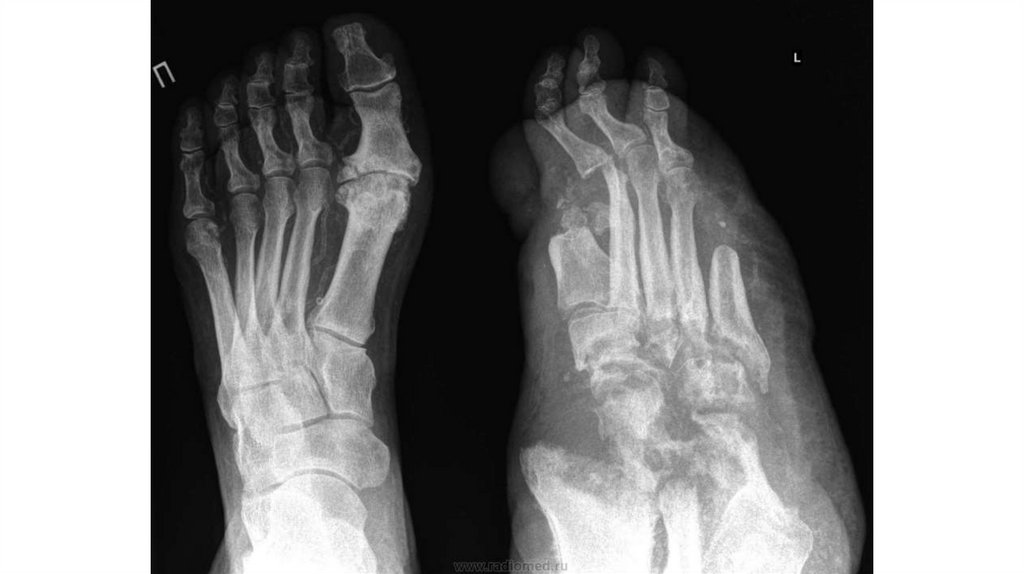

54. Классификация ДНОАП на основании клинической картины, результатов МСКТ/МРТ (E.A.Chantelau, G.Grutzner, 2014)

Стадии/Фазы

Клиника

МСКТ/МРТ признаки

Активная

Умеренно выраженное

Обязательные: отек костного мозга и мягких

стадия

воспаление (отек, локальная тканей, нет нарушения кортикального слоя.

Фаза 0

гипертермия,

иногда

боль, Возможные: субхондральные трабекулярные

повышенный

риск

микротрещины, повреждение связок.

травматизации при ходьбе), нет

выраженных деформаций

Обязательные: переломы с нарушением

Выраженное воспаление (отек, кортикального слоя, отек костного мозга и/или

Фаза 1

локальная гипертермия, иногда отек мягких тканей.

боль, повышенный

Возможные: остеоартрит, кисты, повреждение

травматизации

при

ходьбе), хряща, остеохондроз, внутрисуставной выпот,

выраженная деформация

скопление жидкости в суставах, костные

эрозии/некрозы, лизис кости, деструкция и

фрагментация кости,

вывихи/подвывихи

суставов, повреждение связок,

дислокация

костей.